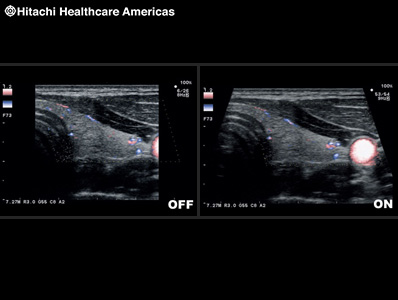

Contrast Harmonic Imaging (CHI) *

To improve understanding of blood flow information, Fujifilm Healthcare offers harmonics enhanced imaging specifically designed for use with contrast agents. The low MI contrast imaging obtained improves signal-to-noise ratio.

* In the USA, contrast-enhanced ultrasound has not been market cleared by the FDA for all imaging applications.